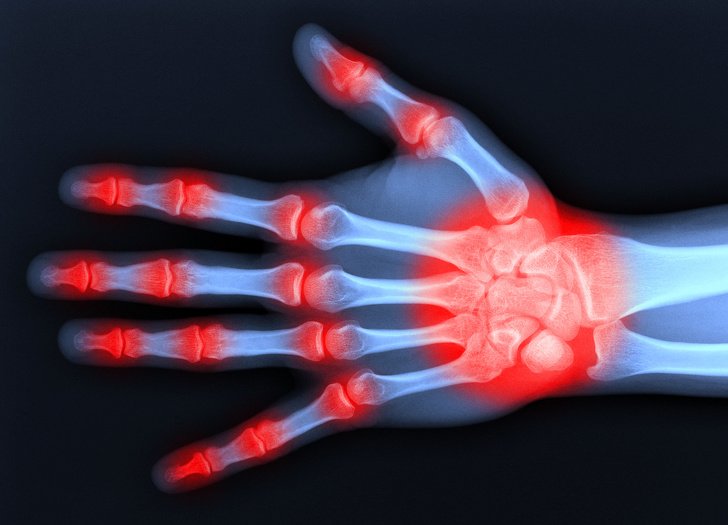

Ревматоїдний артрит навчаться не лише лікувати, а й передбачати

Ревматоїдний артрит – хвороба, при якій люди страждають хронічним запаленням суглобів, яка зачіпає, як правило, коліна, кисті рук, щиколотки, гомілковостопні суглоби. Поки що причини її появи невідомі, а лікування виключно симптоматичне. Однак на початку 2019 року вчені розповіли про ген ELMO1, який може стати ключем до позбавлення від ревматоїдного артриту, оскільки його відключення знижує запалення. В даний час медики шукають препарат, здатний відключати ген, а також розробляють способи його виявлення в організмі людини, що допоможе боротися з хворобою на ранніх стадіях.